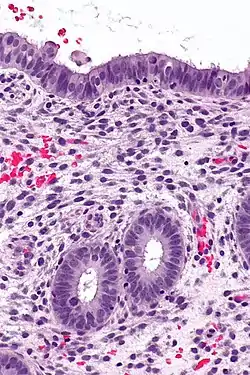

Micrograph of decidualized endometrium due to exogenous progesterone. H&E stain.